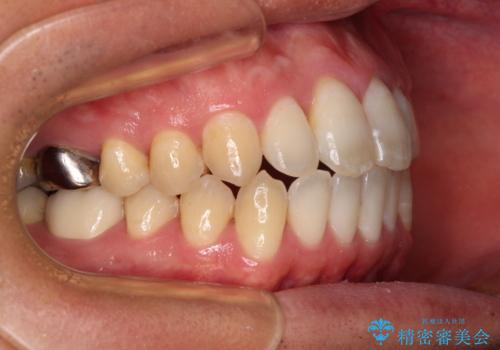

奥歯には目立つ銀歯が多くあるので、矯正治療後には下顎の銀歯をセラミッククラウンやセラミックインレーにより、補綴・修復治療することとしました。

上顎歯列全体を後方に移動させたため、口元の突出感も改善され、装置を外してからは口が閉じやすくなりました。

また、上下犬歯が接触するようになったため、奥歯にストレスのかからない歯ぎしりができるようになり、顎の疲れも改善されました。